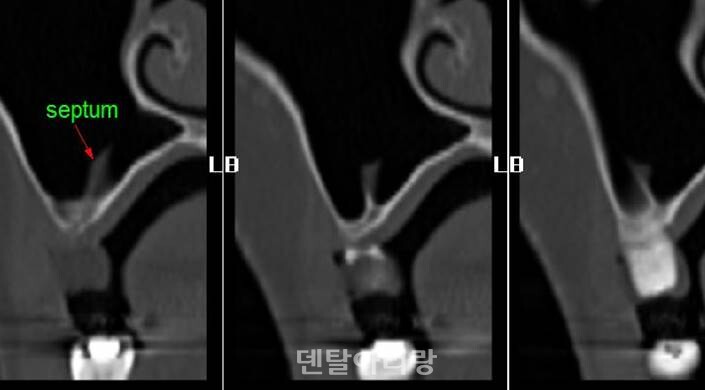

상악동 골이식술 시, 해부학적으로 고려해야 할 요소 중 또다른 하나는 상악동 중격(septum)이다<그림 10>.

△그림 10. 상악동내 중격의 컴퓨터 영상장치 이미지

대부분의 경우에서 상악동 아래 바닥에 중격이 존재하나 그 양상은 매우 다양하다. 상악동의 중격은 바닥벽 뒤쪽 치아뿌리 사이에 주로 나타나며, 1~2%의 경우에 완전하게 분리되어 나뉘어 작은 덧굴(Haller’s cells)을 이루기도 한다.

상악골의 중격은 치아가 있을 때에는 교합력을 분산시키는 역할을 하지만, 나이가 들어 치아가 빠지면서 중격도 점차 없어지기도 한다. 이러한 시상뼈중격(sagittal bony septa)은 평균 2mm의 두께를 가지며, 모양이 매우 다양하다. 상악 구치부 발치시에 치아뿌리의 부서진 조각이 상악동 안으로 들어가 중격에 의해 생긴 오목한 부위에 머무는 경우 이를 제거하는 데 어려움이 생길 수 있으며, 상악동 염증 시 고름(pus)의 배출을 방해할 수도 있다. 또한 임플란트 식립을 위한 상악동 점막 거상술 시, 점막의 찢어짐을 일으킬 수 있어 특히 주의해야 한다. 이를 예방하기 위해 술전 방사선 영상 진단을 통해 중격의 위치와 형태를 진단하고 상악동 측벽 접근법을 시행할 때, 상악동 중격을 중심으로 좌, 우로 나뉘는 2개의 골창을 형성하여 골이식을 시행하는 것이 추천된다<그림 11>.